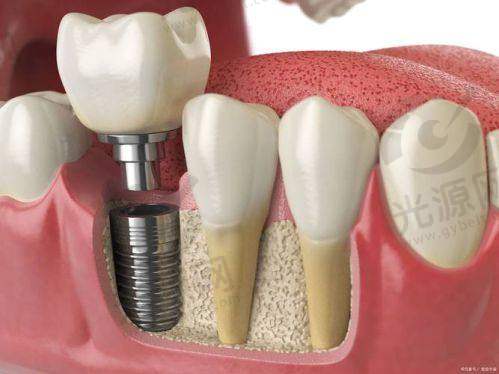

2. 种植牙:依据品牌与材料选择,价格从4599元 - 17000元都有。